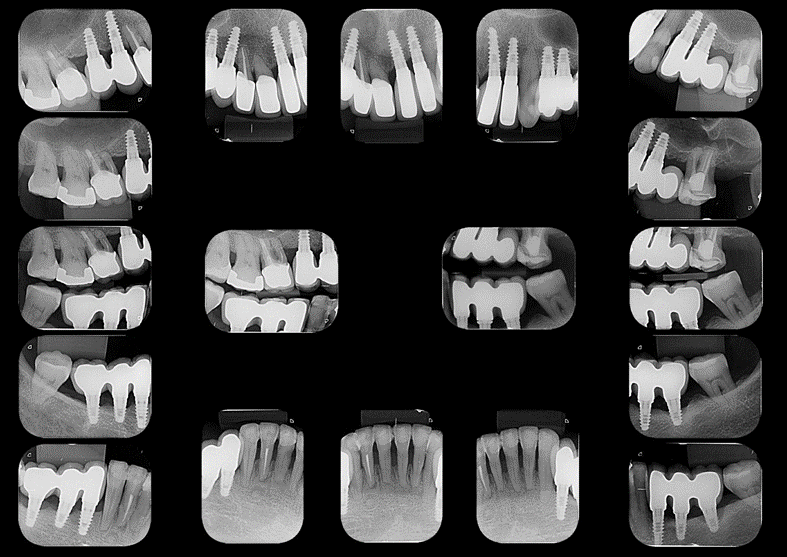

A paciente passou incialmente por tratamento periodontal não cirúrgico previamente à colocação de implantes dentais e reabilitação protética. Para este tratamento, optamos pelo uso de implantes curtos e estreitos em regiões com pouco altura/espessura óssea. Ainda foi utilizada a opção de prótese parcial fixa implantossuportada em cantilever distal, visando evitar procedimentos mais invasivos em região de seio maxilar. Vale ressaltar que embora alguns dentes foram indicados para exodontia, devido a impossibilidade restauradora, a maior parte dos dentes foram passíveis de manutenção. Isto é possível devido a alta previsibilidade da terapia periodontal no que se refere a manutenção de dentes em função, mesmo na presença de significativa perda de inserção.

Após a reabilitação implantossuportada, a paciente foi inserida em terapia periodontal de suporte com retornos regulares visando diagnóstico de infecção periodontal/peri-implantar, prevenção destas condições e tratamento precoce em casos de recidiva da doença periodontal e início de doença peri-implantar. Neste sentido, Herrera et al. (2023) preconizam que a prevenção de doenças peri-implantares deve começar quando os implantes dentários são planejados, colocados cirurgicamente e carregados protéticamente.

Esta abordagem permitiu, em 2018, o diagnóstico de doença peri-implantar no implante colocado na região do dente 36 e, posteriormente ao tratamento desta condição, pode-se observar a estabilidade do nível ósseo nos acompanhamentos radiográficos nos anos de 2021 e 2023.

O acompanhamento longitudinal desta paciente ilustra a possibilidade de manutenção de dentes, mesmo com suporte periodontal reduzido, associada a reabilitação implantossuportada. Neste tipo de abordagem, a terapia periodontal age de forma sinérgica à reabilitação implantossuportada, garantindo o sucesso do tratamento reabilitador, desde que os pacientes realizem controles periódicos.